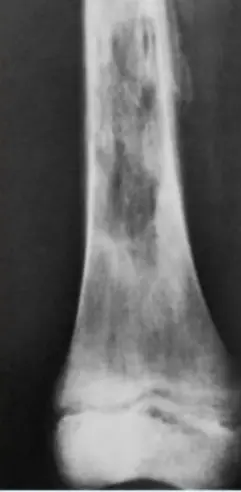

Ewing Sarcoma

Clinical Features:

- Occurs in children

- Throbbing pain

- Can be confused with chronic osteomyelitis

- Poor prognosis

Clinical Cases:

-

11-year-old presented with symptoms - diagnosis on imaging

- Diagnosis: Ewing sarcoma

Case scenario provided with picture